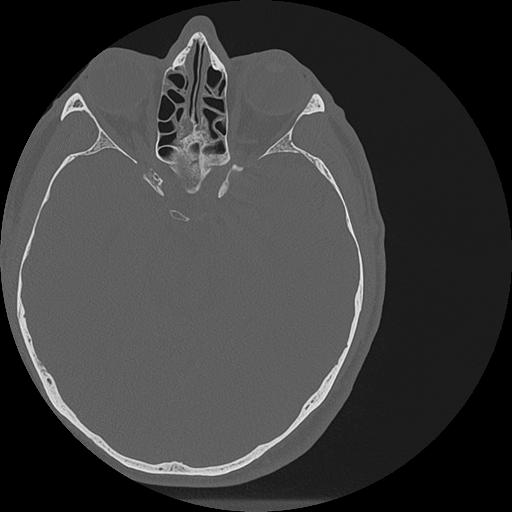

7 HUESO,,Vol,0.5,HUESO,,